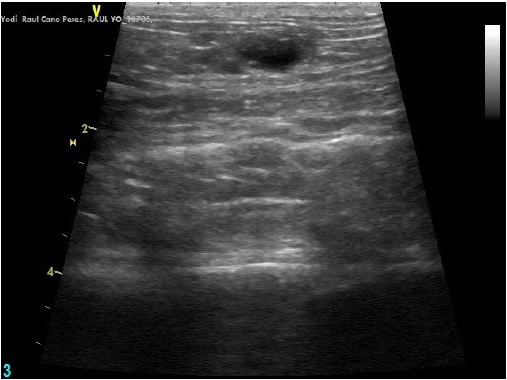

El siguiente paso en nuestro protocolo fue realizar una ecografía abdominal con la que finalmente confirmamos nuestras sospechas: Yodi tenía quistes en ambos ovarios, lo que le producía un desequilibrio hormonal importante. La solución, por lo tanto, fue pasar por quirófano: esterilizándola sus problemas deberían solucionarse.